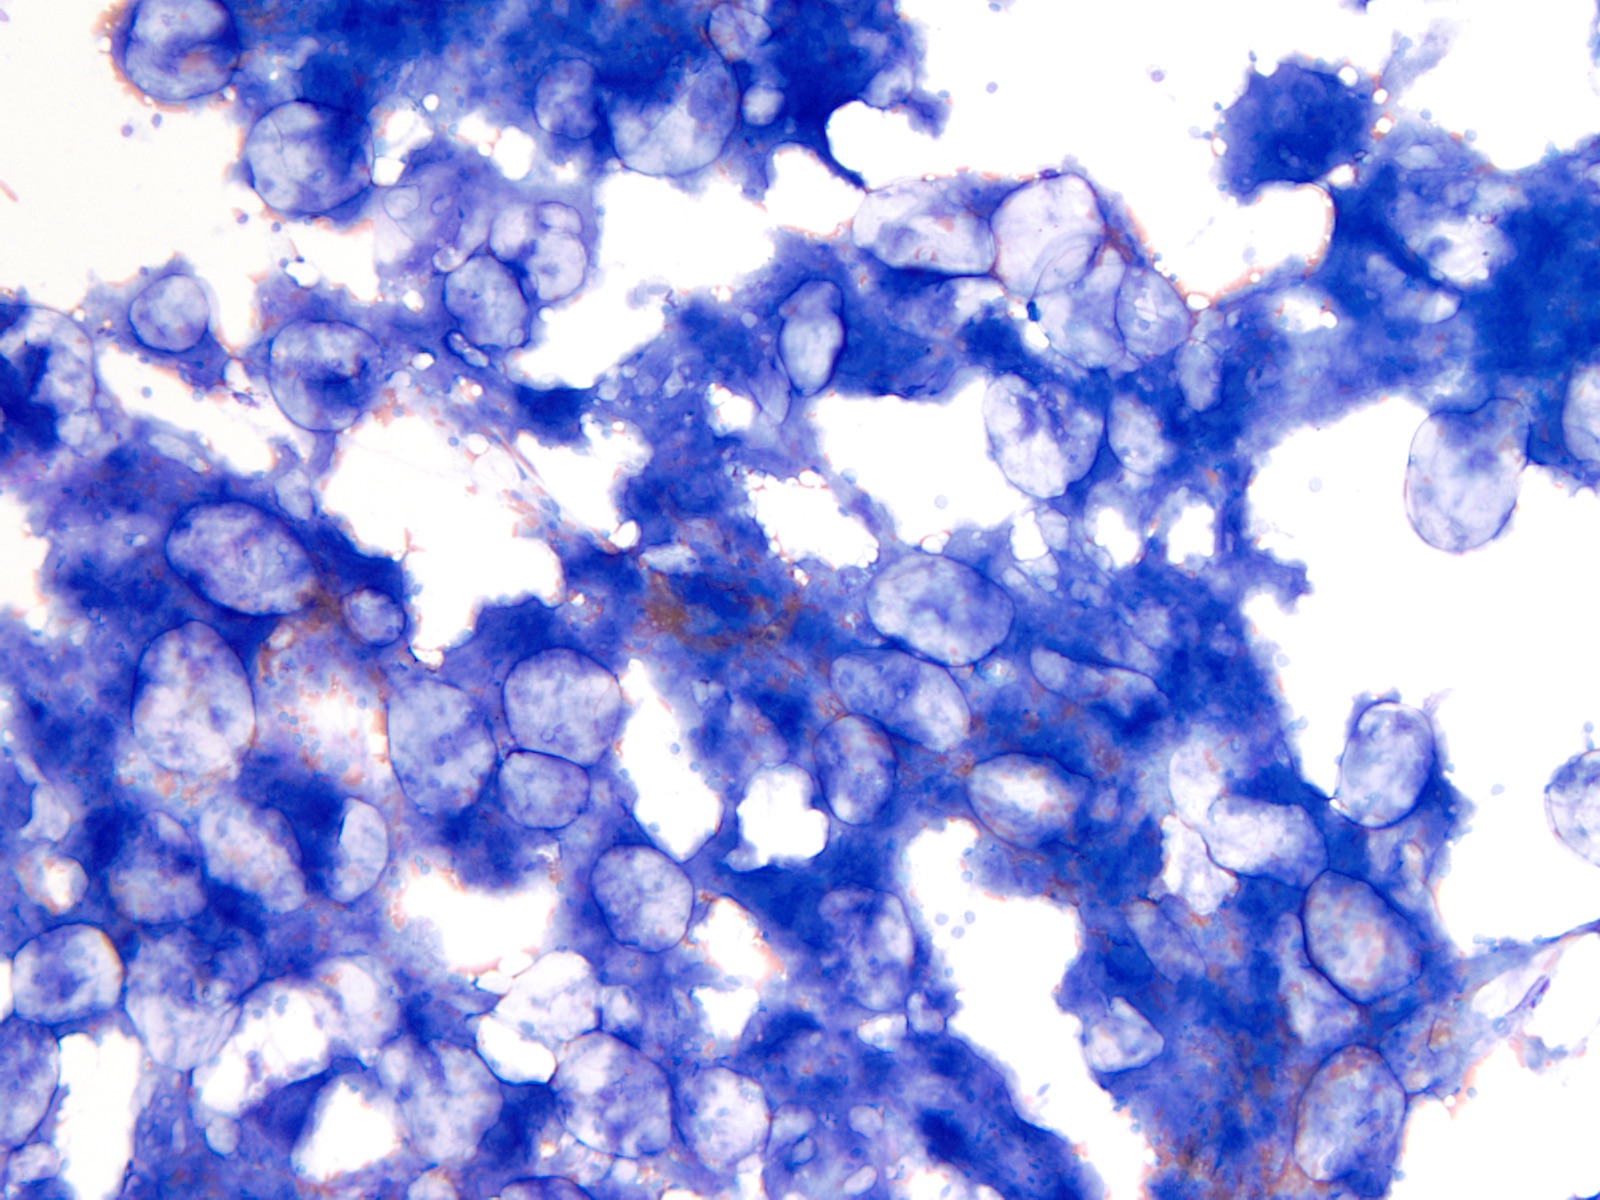

Cytology description

- Cytology can assess plasma cell morphology (e.g., mature, immature, plasmablastic) but number of plasma cells present may vary substantially from the core biopsy

- Mature plasma cells: oval with abundant basophilic cytoplasm, perinuclear hof, round eccentric nuclei, clock face chromatin and indiscernible nucleoli

- Immature plasma cells: higher nuclear to cytoplasmic ratio, more abundant cytoplasm and hof region compared to plasmablastic, more dispersed chromatin, often prominent nucleoli

- Plasmablastic: less abundant cytoplasm with little or no hof region, fine reticular chromatin, large nucleus (> 10 microns) or large nucleolus (> 2 microns) (Blood 1998;91:2501)

- Pleomorphic: multinucleated, polylobated

- Rare cases may have small, lymphoid appearing plasma cells or plasma cells with marked nuclear lobation

- Immature or pleomorphic features are rare in reactive plasma cell proliferations

- Morphologic features:

- Mott cells / morula cells: multiple grape-like cytoplasmic inclusions comprised of crystalized immunoglobulin

- Russell bodies: hyaline intracytoplasmic inclusions

- Flame cells: vermillion staining glycogen rich IgA in cytoplasmic projections (American Society of Hematology: Flame Cells in Multiple Myeloma [Accessed 26 May 2022])

- Pseudo-Gaucher cells / thesaurocytes: overstuffed fibrils (J Clin Pathol 1976;29:916)

- Cytoplasmic crystals: occasional in myeloma, common in adult Fanconi syndrome (Am J Clin Pathol 1983;80:224)

- Dutcher body: pale staining immunoglobulin filled cytoplasm invaginating into the nucleus and appearing as an intranuclear inclusion, single and usually large, more common in IgA myeloma